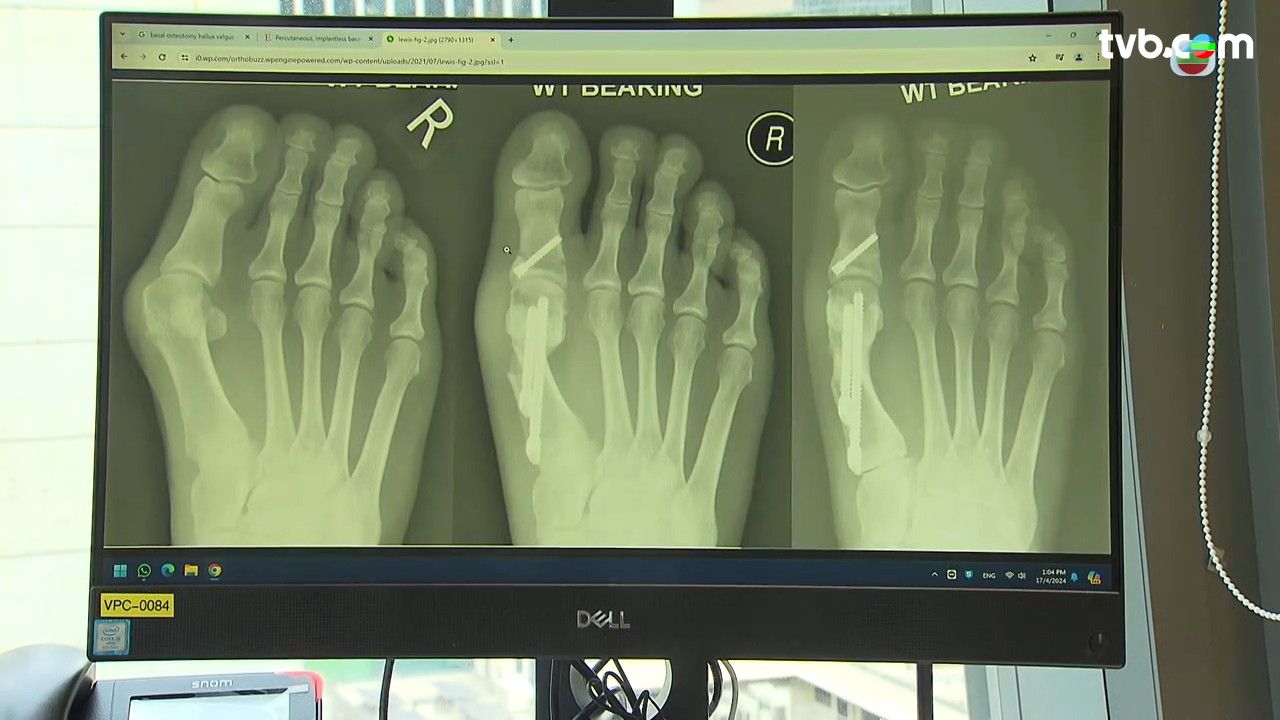

拇趾外翻是香港最常見的足部疾病,女性患者較多,因為拇趾的蹠骨移位,令拇趾向外側,前足腳趾變形,變相令走路壓力增加。拇趾外翻會令趾骨出現紅腫、發炎和疼痛。

手術可以蹠骨移位問題慢慢改善,但怎樣情況就要做手術?當你拇趾外翻: